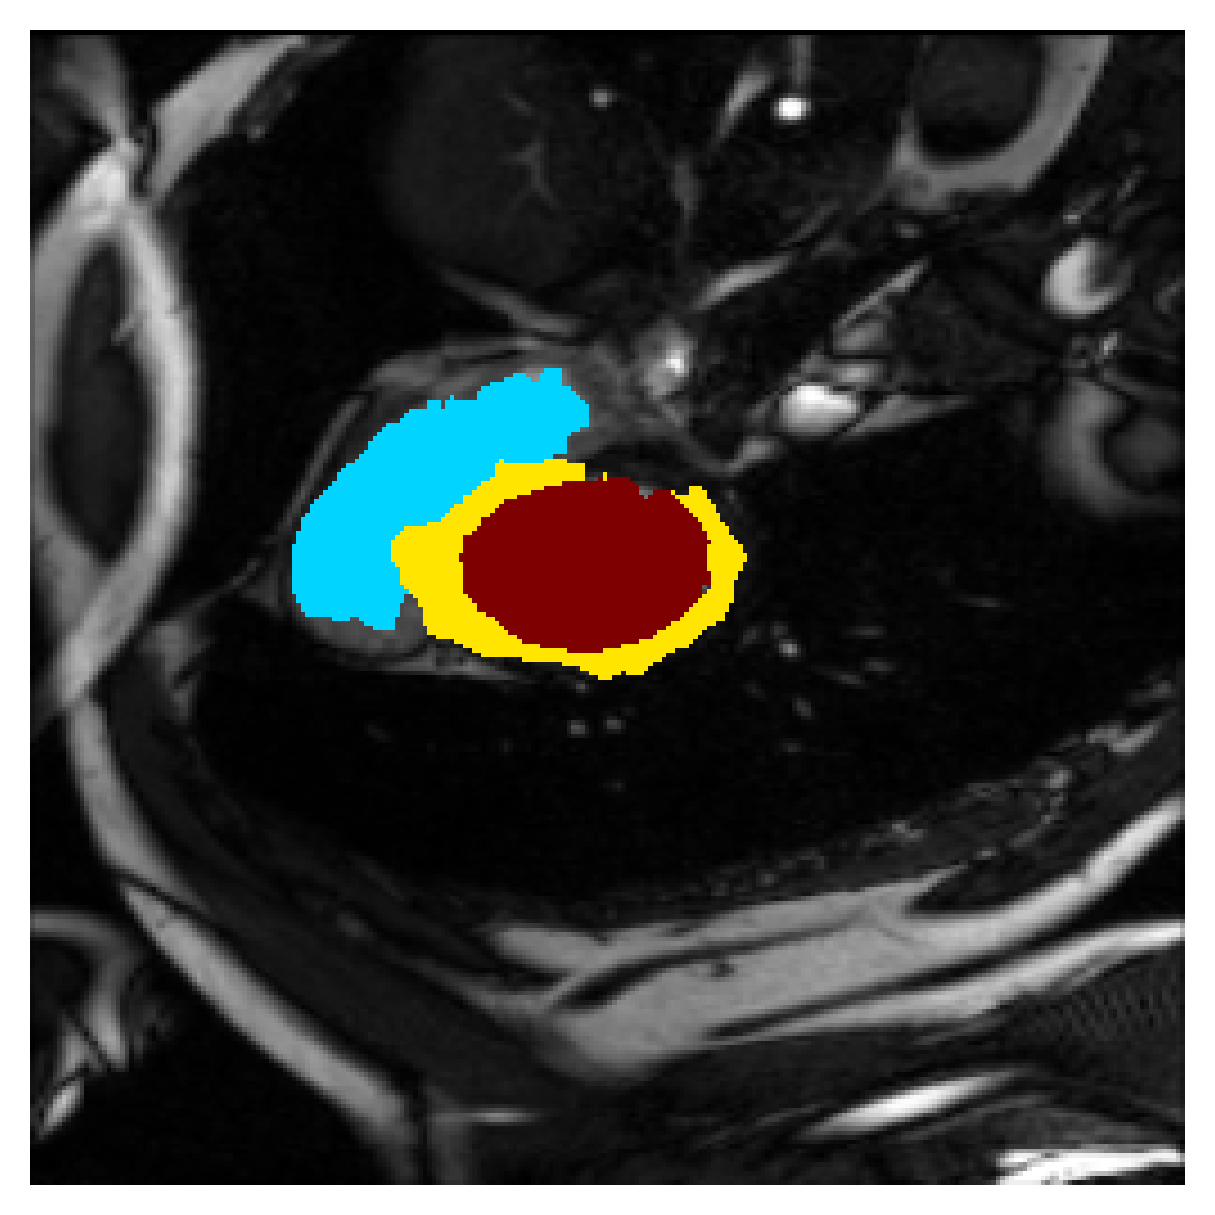

Qualitative comparison

In Figure 6 we provide qualitative results on a number of randomly chosen test set slices. Upon visual inspection, we can observe that training with the intensity-aware distances (particularly with and ) follows the image gradients better and is better at recovering the underlying shape than the Euclidean version. The CRF-loss seems to recover the shape of the myocardium and left ventricle to some extent, but fails entirely on the right ventricle.